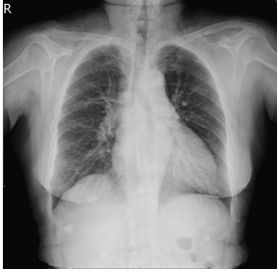

2. A 27-year-old woman had productive cough for one month.